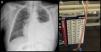

This was an 89-year-old man, non-smoker with a history of arterial hypertension, dyslipidemia, and stage IV chronic kidney disease, with atrophic left kidney due to left renal artery stenosis. He was receiving anticoagulation for chronic atrial fibrillation, and had undergone transurethral resection for benign prostatic hypertrophy, and pulmonary thromboembolism in 2015. He presented in the emergency room for progressive worsening of dyspnea and pain in the left hemithorax, without no previous fever or catarrh. Physical examination showed tachyarrhythmia without murmurs, and auscultation of the lungs revealed signs of left PE. Chest X-ray showed PE occupying the lower two thirds of the hemithorax (Fig. 1). Laboratory tests showed 7000 leukocytes with 82.7% neutrophils; creatinine 2.15mg/dl; total protein 5.56g/dl; albumin 2.70g/dl; LDH: 178IU/l; and CRP: 18mg/l. Ultrasound and computed tomography (CT) of the abdomen and pelvis showed no signs of hydronephrosis nor free liquid, and left kidney measuring 9cm with irregular contour and atrophic appearance, and a small amount of peri-renal fluid. Renal Doppler showed intra-renal flows with increased resistance indices in both renal arteries, indicative of severe stenosis. Chest ultrasound showed moderate PE without septations, and a diagnostic and therapeutic thoracentesis was performed, yielding 1200ml of cloudy, amber-colored PF, smelling of urine. The PF protein/serum protein ratio was 0.69 and the PF LDH/serum LDH ratio was 0.7, confirming the presence of exudate; pH was 7.11. Creatinine in PF was 3.4mg/dl, with PF creatinine/serum creatinine ratio of 1.58, confirming the suspicion of urinothorax. Microbiological cultures and cytology were negative. Thoracentesis and Pleur-evac® were performed 5 times in the following 2 months due to recurrent PE. An intravenous dose of rifampicin was administered, and the PF drained by the Pleur-evac® was confirmed to be copper-colored, so a tunneled pleural catheter was implanted, which remained in place for 2 months, requiring 2 changes of the recipient every week. The patient died of multiple comorbidities and kidney failure not resolved by dialysis.